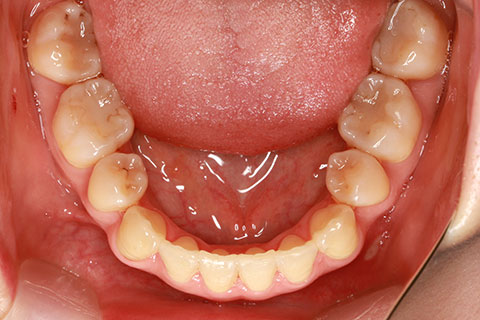

矯正期間18ヶ月

フルリンガル矯正2(上下の歯を舌側矯正で治療)

治療前

治療中

治療後

- 年齢・性別

- 42歳男性

- 治療期間

- 1年6ヶ月

- 抜歯

- なし

- 治療費

- 120万円(税込み)

- 備考

- マルチブラケットを用いた矯正治療

- 治療内容

- 反対咬合をフルリンガル矯正治療にて改善

- 施術の副作用(リスク)

- 表側矯正と比較して、歯根の角度を確立する「トルク」の力がかかりにくい。